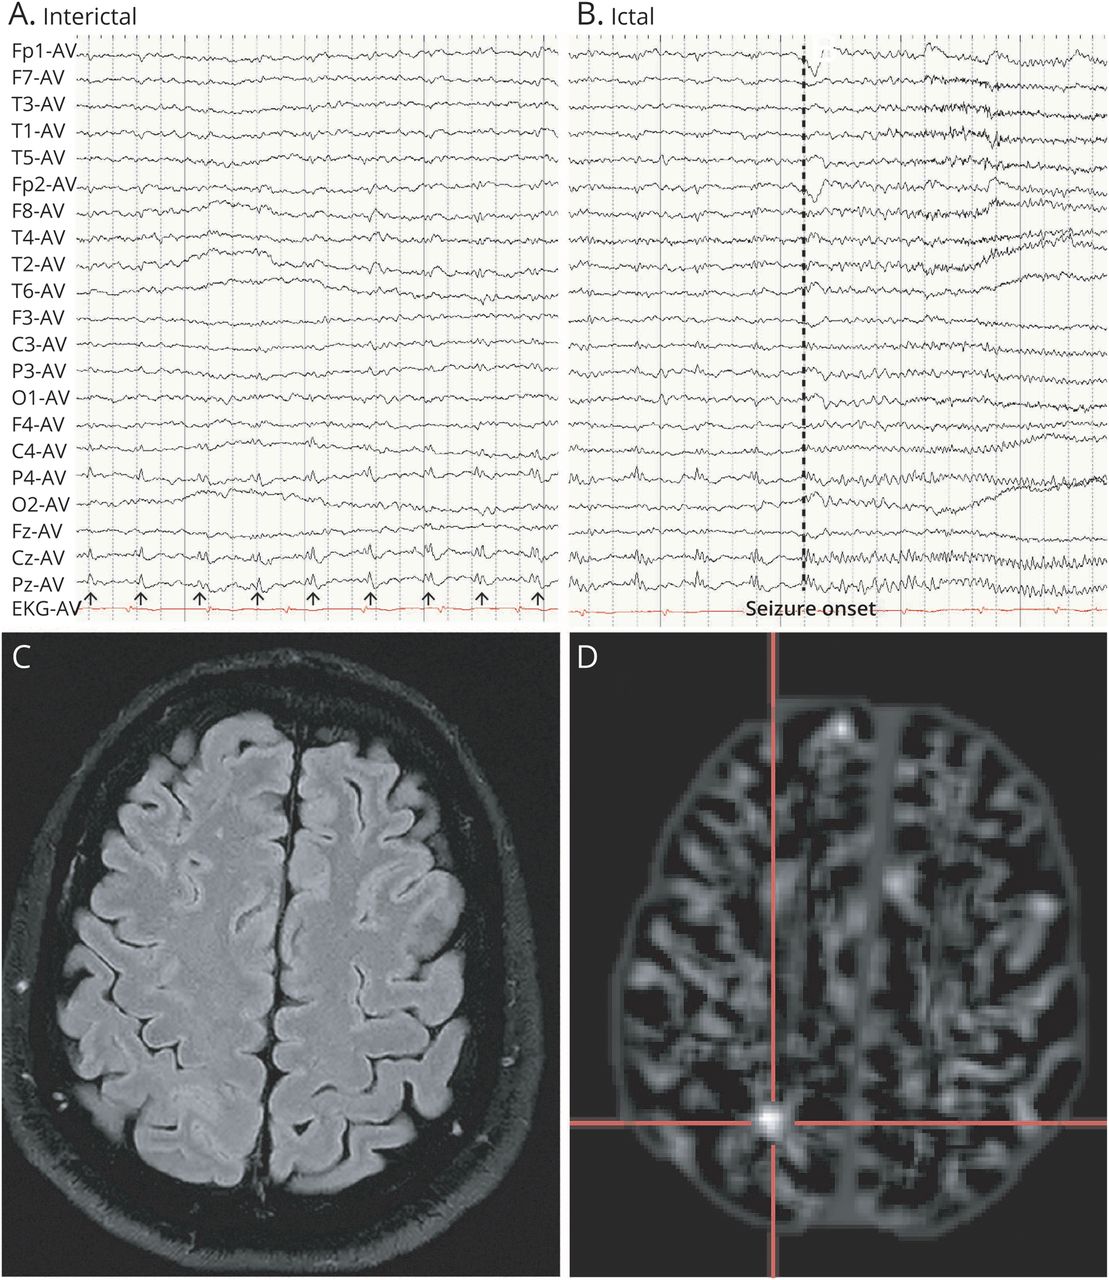

清醒和睡眠脑电图背景是正常的。在他发作脑电图,断断续续的红色正确centroparietal地区占主导地位的(P4、Pz、Cz) (图1一个)。在习惯性的攻击,更频繁的红军对centroparietal地区被发现,对应于躯体感觉气场。随后右侧焦快速痫性活动与主音的左腿的姿态。FBTCSs是伴随着对centroparietal焦快速活动地区,其次是广义飙升和脑电图波(图1 b)。

(一)样发作脑电图(时间基地30毫米/秒,灵敏度10μV /毫米)显示有节奏的痫性放电(箭头),以正确的centroparietal地区。(B)猝发的脑电图(时间基地30毫米/秒,灵敏度10μV /毫米)显示红色越来越频繁,其次是对正确的centroparietal地区快速痫性放电。虚线标志着癫痫发作时临床观察癫痫症状(主音的姿态左腿)开始。(C)复审的高分辨率核磁共振成像显示微妙的皮质增厚最大的底部中央后沟。(D)分布的形态学MRI后处理进一步揭示异常在中央后沟的深度,中央后回的一部分,和顶叶小叶。

尽管最初-核磁共振报告,我们仍然怀疑异常后中央沟的符号学和脑电图的发现。那些将要动手术多学科会议期间,我们重新审视了高分辨率核磁共振成像的特别关注中央后区。微妙的皮质增厚最大的底部沟被怀疑(图1 c)。分布MRI后处理进一步证实了异常最大的底部中央后沟(图1 d)。pet mri coregistration显示轻度代谢减退在同一区域(eFigure 1 d,links.lww.com/WNL/B790)。考虑到损伤接近雄辩的地区(感觉运动皮层和顶叶小叶),颅内电极植入。

FCD drug-refractory请耐心是一个常见的病因。4,7在我们的病人中,高度本地化的红色脑电图作为一个重要的诊断线索。10红色指的是刻板的,锋利的海浪有节奏的序列或者峰值持续> 1秒。11,12这脑电图的发现是在1996年首次提出FCD的生物标志物,1140%的敏感性-50%,特异性95% -100%头皮脑电图。12识别脑电图的生物标记使我们重新审视病变的高分辨率磁共振成像在搜索。特别是,我们的病人有一个高度本地化的亚型II型FCD, BOSD药物耐火度著称,但优秀的手术结果。10BOSD很容易错过鉴于其微妙的MRI异常,包括皮质增厚,灰白色结模糊,和皮层下hyperintensity最大沟的深度。磁共振成像后处理和pet MRI coregistration进一步协助识别损伤,增加了对手术治疗的信心。